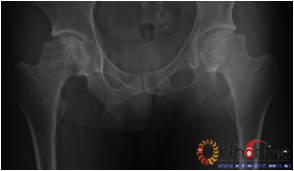

图1 女,22岁,(1)双侧股骨头坏死右侧B型,左侧C1型;(2)打压植骨术(加入BMP2)后5年,CT显示植骨生长良好,关节功能正常(Harris评分96分);(3)术后7年关节功能维持正常,股骨头维持正常外形